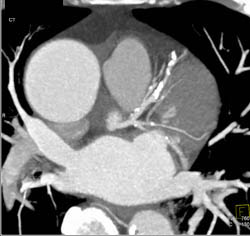

Aneurysm of Left Circumflex Coronary Artery